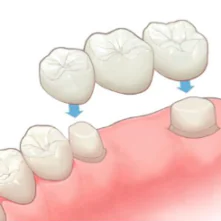

ブリッジ

ブリッジ治療は外科処置を行わない固定式の治療法です。歯を失った部分に人工歯を固定し、両隣の健康な歯を支えとして利用します。この治療法は入れ歯よりもしっかりとした咬み心地と自然な見た目が得られますが、支えとする歯に一定の負担がかかるというデメリットも存在します。

ブリッジ治療は外科処置を行わない固定式の治療法です。歯を失った部分に人工歯を固定し、両隣の健康な歯を支えとして利用します。この治療法は入れ歯よりもしっかりとした咬み心地と自然な見た目が得られますが、支えとする歯に一定の負担がかかるというデメリットも存在します。